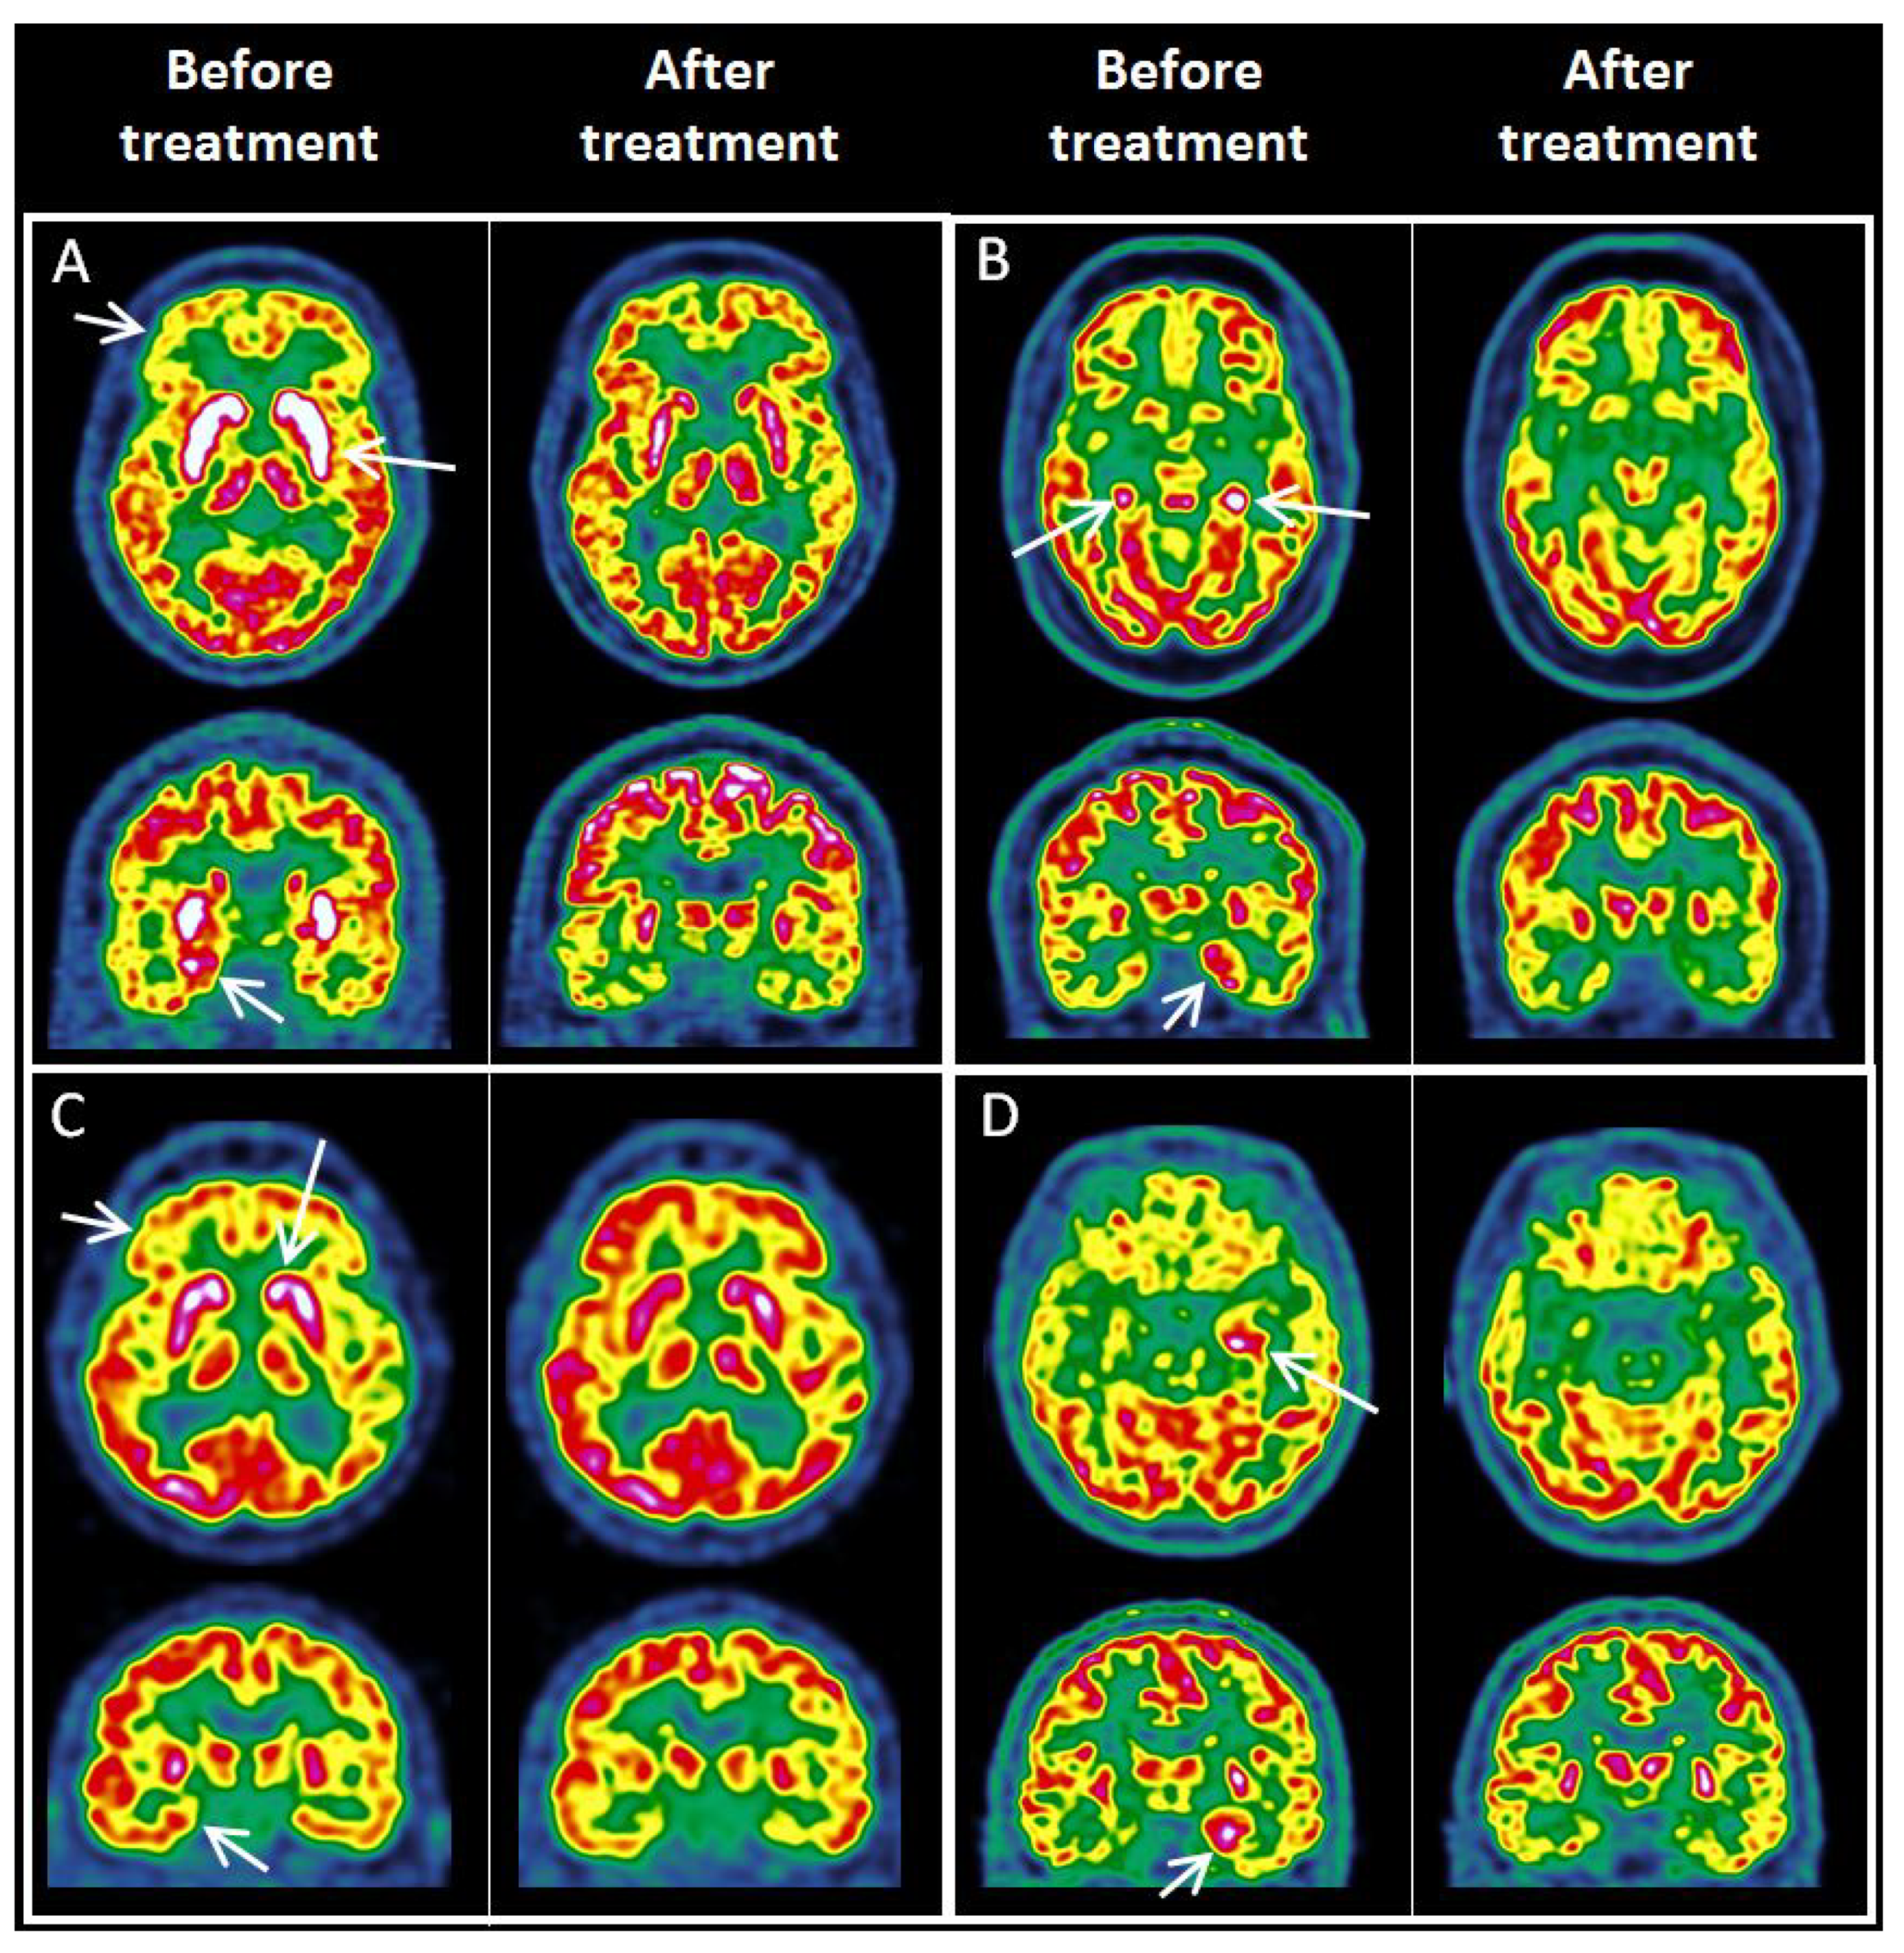

3.5. FDG PET in LGI1, NMDAR, GAD and CASPR2 Antibody Subtypes

3.6. Treated vs. Untreated Patients